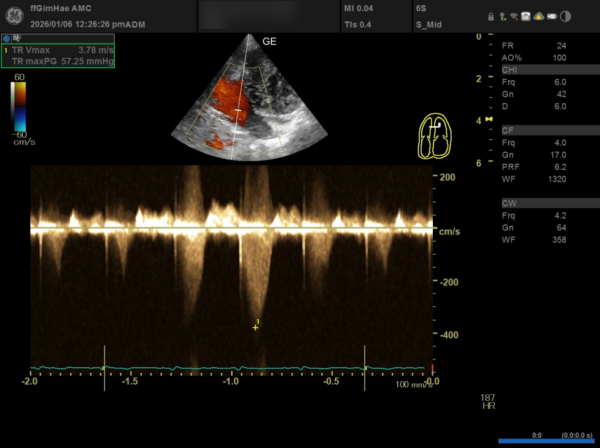

① TR(삼첨판 역류) 수치

TR Vmax: 3.78m/s (기준치인 3.4m/s를 훨씬 초과)

TR maxPG: 57.25mmHg

3b5a6cb0f0735f89df35c2e207e2d7ba_1776391152_4628.png